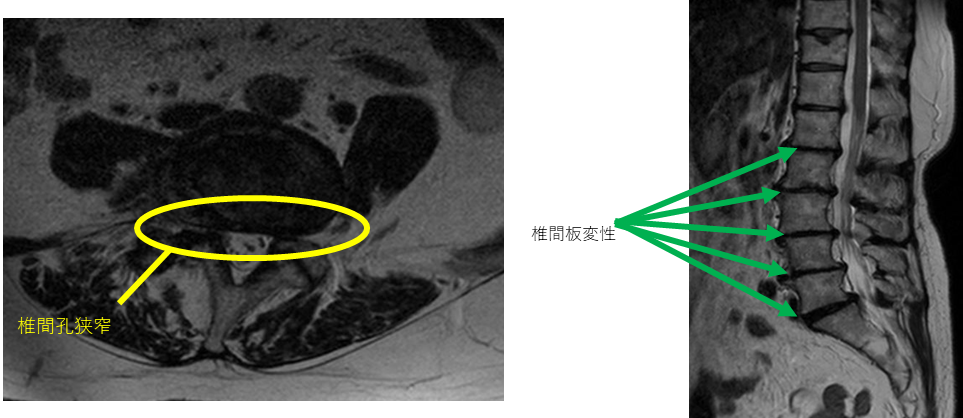

L1/2: 椎間板変性症、両椎間孔狭窄

L2/3: 椎間板変性症、右椎間孔狭窄

L3/4: 椎間板変性症、両椎間孔狭窄

L4/5: 椎間板変性症、両椎間孔狭窄

以上の事が画像上認められます。

L1/2、2/3、3/4、4/5、5/S椎間板変性症、椎間孔狭窄 を認め、主症状の原因の可能性が高い。